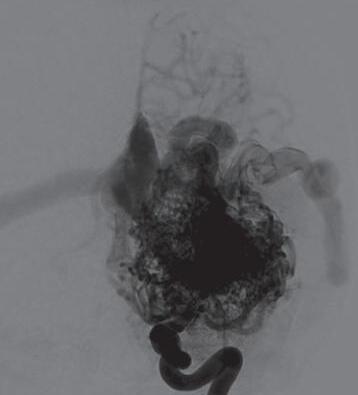

Fig. 1-16. RNM encéfalo T1 com contraste: (a) Coronal e (b) axial demonstrando MAV grau 4 frontoparietal esquerda. (c,d) Arteriografia cerebral AP mostrando a irrigação pelos ramos da cerebral anterior e média esquerda, além da cerebral anterior direita, com drenagem superficial para o seio sagital superior. Seta azul apontando para o nidus da MAV.